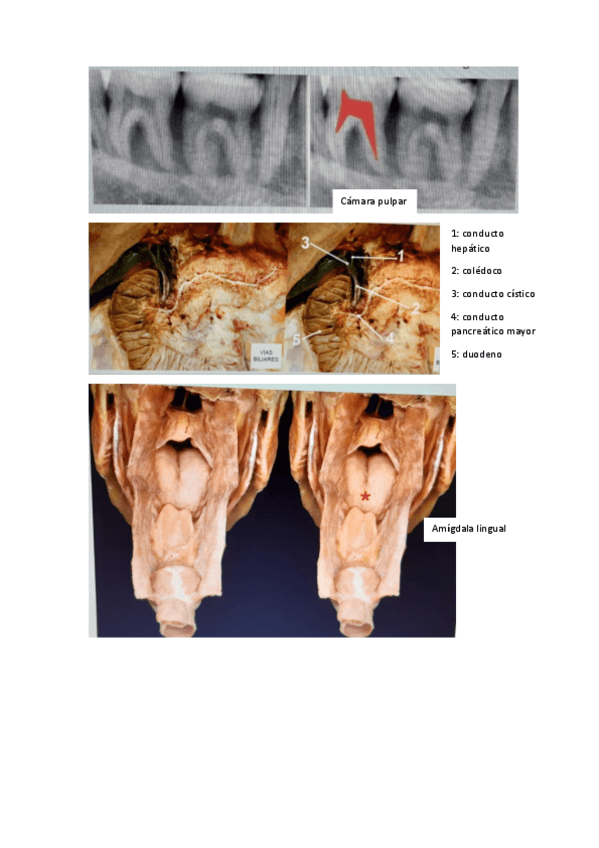

Apuntes - aparatodigetsivo.pdf